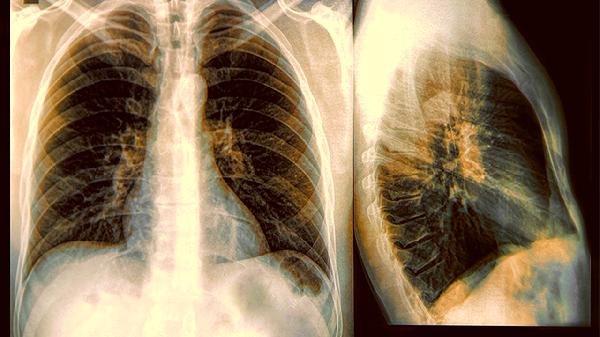

早上刷牙时咳嗽带血丝,爬个楼梯气喘得像跑了马拉松,这些信号可能不是单纯的身体抗议。当烟草烟雾中的焦油悄悄在肺泡上作画,有些人的肺部防御工事会比旁人溃败得更快。关于吸烟与肺癌的纠缠,最.新研究撕开了一道耐人寻味的观察窗口。

1.肺功能储备先天不足

同样每天一包烟,有人六十岁还能跑马拉松,有人四十岁就查出了毛玻璃结节。基因检测显示,部分人群的谷胱甘肽硫转移酶活性天生较弱,这支负责清除烟草毒素的生化特种部队,在有些人体内只有半额编制。

2.免疫巡逻队经常开小差

支气管黏膜上的纤毛本就像永不停歇的扫地机器人,但在长期烟雾熏染下,有些人纤毛倒伏的速度比常人快好几倍。更糟的是,烟雾还会策反免疫细胞,让本应清除癌前病变的巨噬细胞变成了肿瘤的帮凶。